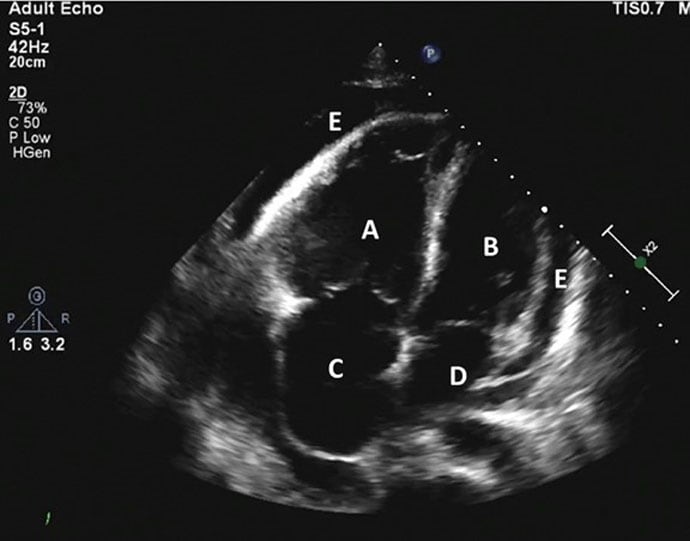

Le flutter commun est une arythmie fréquente dont l'origine est l'oreillette droite Le succès de l'ablation a été défini par l'absence de récidive d'arythmie atriale (FA, flutter ou tachycardie atriale) de plus de 30 secondes, trois mois après ablation (blanking period). Après avoir introduit des cathéters dans la veine fémorale, l'isthme cavo tricuspide est ciblé